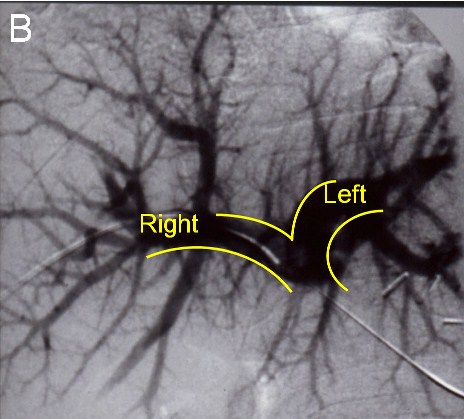

| (B) Before the next operation, a portal vein embolization is done: Venogram showing a normal portal vein prior to embolization |